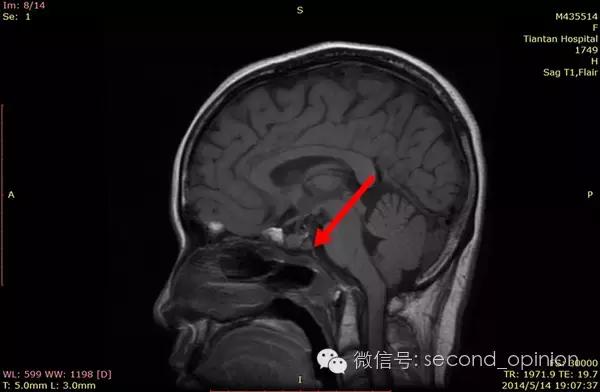

至2014年1月,出现左耳耳鸣,表现为低调杂音,未发现听力明显降落,偶有脸部麻木,无面瘫。行MRI检查,颅内占位范围约60*45*47mm。2014年2月2日第一次手术,行内镜导航下经蝶窦颅底肿瘤切除术,切除体积约50*45*50mm,手术顺利,术后头痛症状消失。左耳低调耳鸣术后消失两周后再次出现,右耳术后出现偶发轻度耳鸣。2014年5月4日第二次手术,行内镜口鼻蝶入路脊索瘤切除术,切除肿瘤体积45*40*50mm,过程顺利,术后耳鸣消失,病情稳定后出院。

2014年9月1日MRI(手术治疗前)

质子治疗前

2015年1月25日 对比质子治疗之前增强核磁共振影像无明显变化,脊索瘤放疗后变化缓慢,建议3月后继续复查。

2015年04月01日 对比增强核磁共振影像,同第一次复查。

2015年06月03日 对比增强核磁共振影像,对比第三次复查,肿瘤略有缩小。

质子治疗后第四次复查

目前患者生活质量良好,无复发转移。